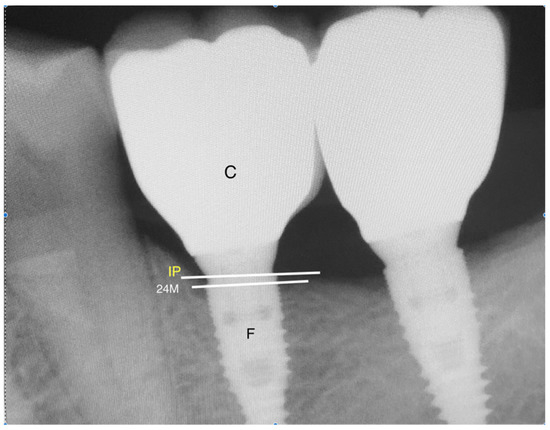

The patients were divided into two groups on the basis of the implant system used, which were either NT or MC collar-implant-design. The surgical protocol was attempted by the same operator, starting with septic technique and chlorhexidine 0.2% mouthwash for 1 min preoperatively. Afterward, a conservative flap was raised under local anesthesia, and the bed was drilled using a low-speed contra-angle handpiece and cooling with sterile saline (0.9% NaCl) following the implant system protocol. All the implants were inserted with a torque of 30–45 Ncm (0.30–0.45 Nm), and cover screws were placed. The implant sizes ranged from 9 to 12 mm in length and 4.0–4.5 mm in diameter. Single interrupted sutures were placed to close the flap, and an immediate periapical radiograph was taken using a long cone positioner to assure proper and standardized angulation. A postoperative antibiotic for 5 days, analgesics, and chlorhexidine 0.2% mouth wash were prescribed. The periapical radiographs were assessed by the same assistant, and the bone level was calculated from the head of the cover screw going more apically at the mesial and distal aspect of the implant. An immediate postoperative radiograph was compared to the 24-month recall periapical radiograph for marginal bone loss (Figure 2). All the prosthetics were screw-retained single crowns, using Ti-base abutments and zirconium crowns. The dentogengival health status and the incidence of peri-implant mucositis were followed through the dental charts.

The marginal bone level (MBL) was compared on the images immediately after the implant placement and at the 24-month recall visit looking for any changes at a marginal bone level calculated by millimeters through the digital imaging system (radio-visiography analysis). The mean and frequencies of the variables were obtained, and a chi-square test was performed to find a correlation of MBL with various factors.

Figure 2. A periapical digital radiograph at 24-month recall; F, implant fixture; IP, implant peak; C, crown; 24M, bone level at 24-month recall visit.